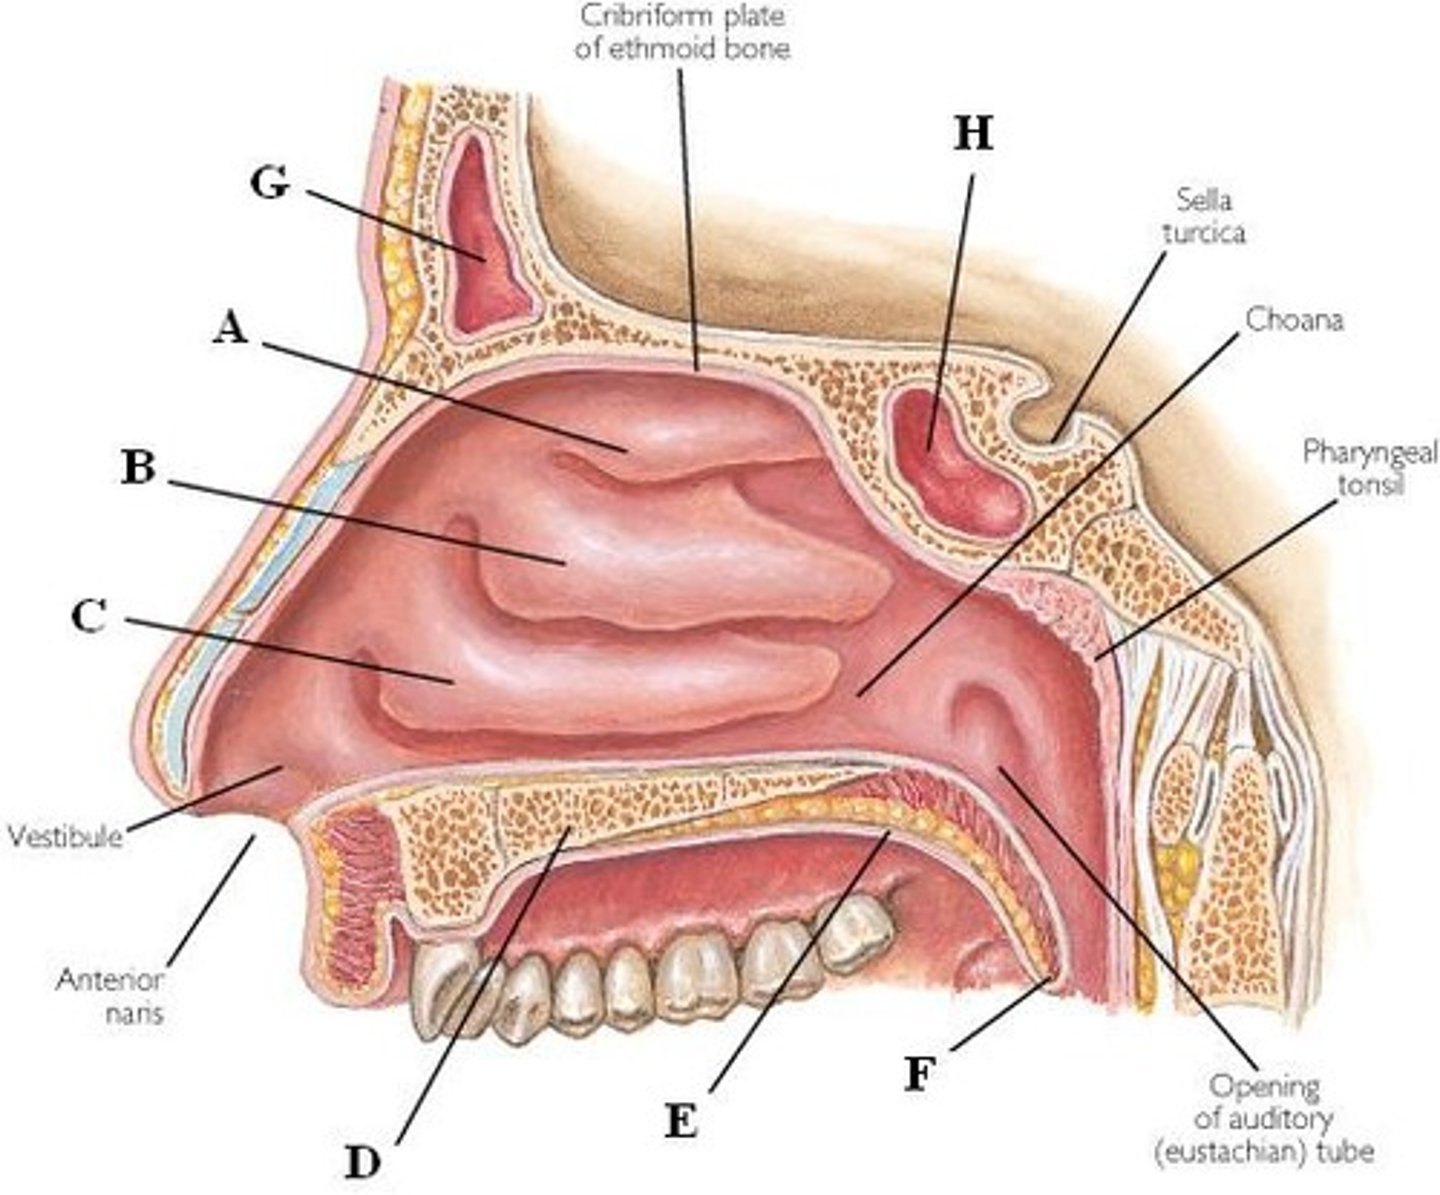

superior nasal conchae

Name A

middle nasal conchae

Name B

inferior nasal conchae

Name C